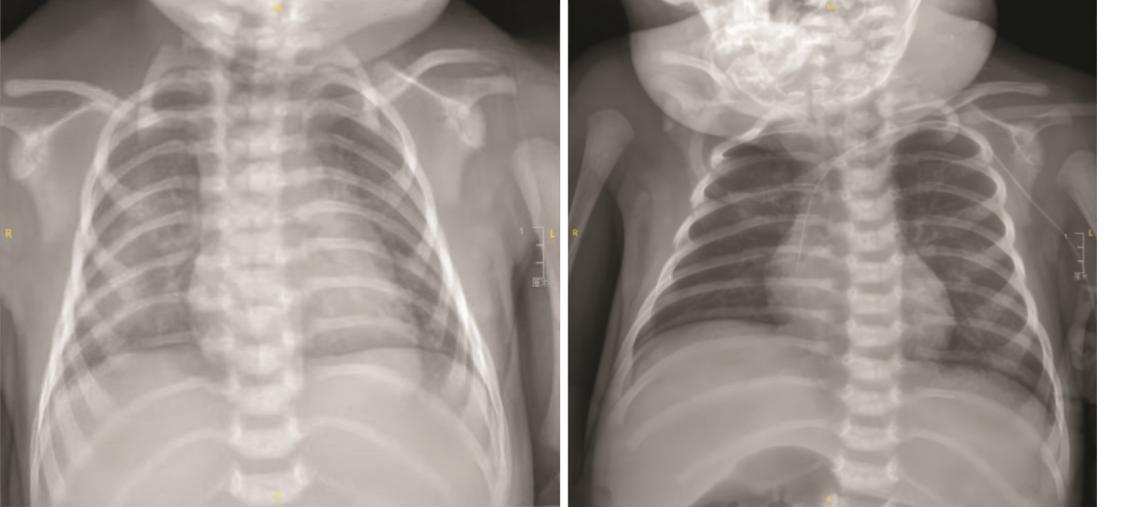

侯丽, 尹琳琳, 蒋林, 等. 新生儿一过性重症肌无力1例并文献复习[J]. 中华新生儿科杂志(中英文), 2024, 39(4):219-223. doi: 10.3760/cma.j.issn.2096-2932.2024.04.006.